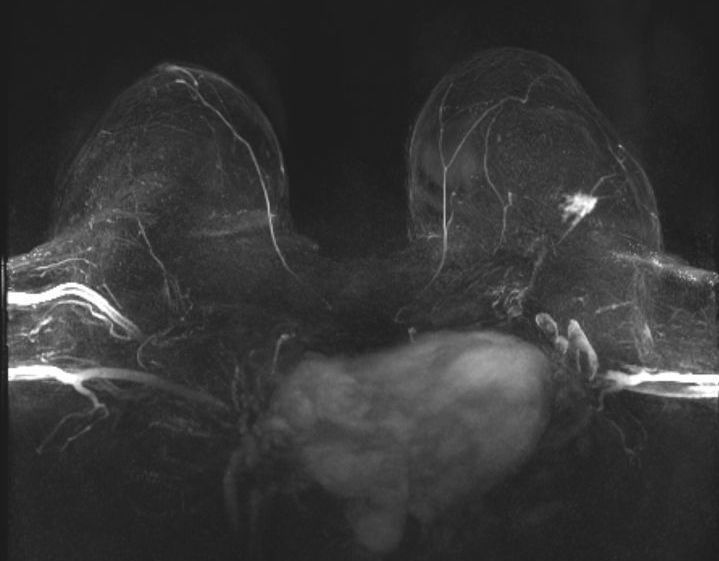

Mamma-MRT als genauestes Verfahren in der Früherkennung/Vorsorge und Nachsorge

Die Mamma-MRT (Magnetresonanztomographie) ist eine wichtige Methode zur Untersuchung der Brust und wird bei verschiedenen Indikationen eingesetzt, darunter bei Patientinnen mit einem erhöhten Risiko, an Brustkrebs zu erkranken, bei unklaren Befunden in der Mammographie oder Sonographie, im Rahmen des Stagings bei bereits bekanntem Mammakarzinom sowie in der Nachsorge bei Verdacht auf ein Lokalrezidiv. Die Befundung erfolgt in Befundkategorien analog zu dem BI-RADS-System, das eine standardisierte Einteilung in verschiedene Kategorien vorsieht. In Deutschland werden die Kosten für eine Mamma-MRT von den gesetzlichen Krankenkassen nur übernommen, wenn die entsprechenden Voraussetzungen erfüllt sind.